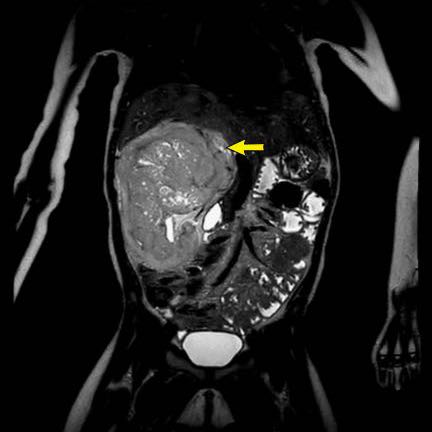

Ca lâm sàng 1

Hình ảnh chuỗi xung T2W mặt phẳng coronal cho thấy một khối u không đồng nhất ở thận trái với các thành phần nang nhỏ.

Khối u ngấm thuốc kém hơn so với phần nhu mô thận bình thường còn lại ở ngoại vi.

Các thành phần đặc của khối u cho thấy hạn chế khuếch tán rõ rệt (mũi tên).

Đây là u Wilms ở bé trai năm tuổi. Hóa trị tiền phẫu được thực hiện theo phác đồ Umbrella của SIOP-RTSG, sau đó tiến hành cắt thận.